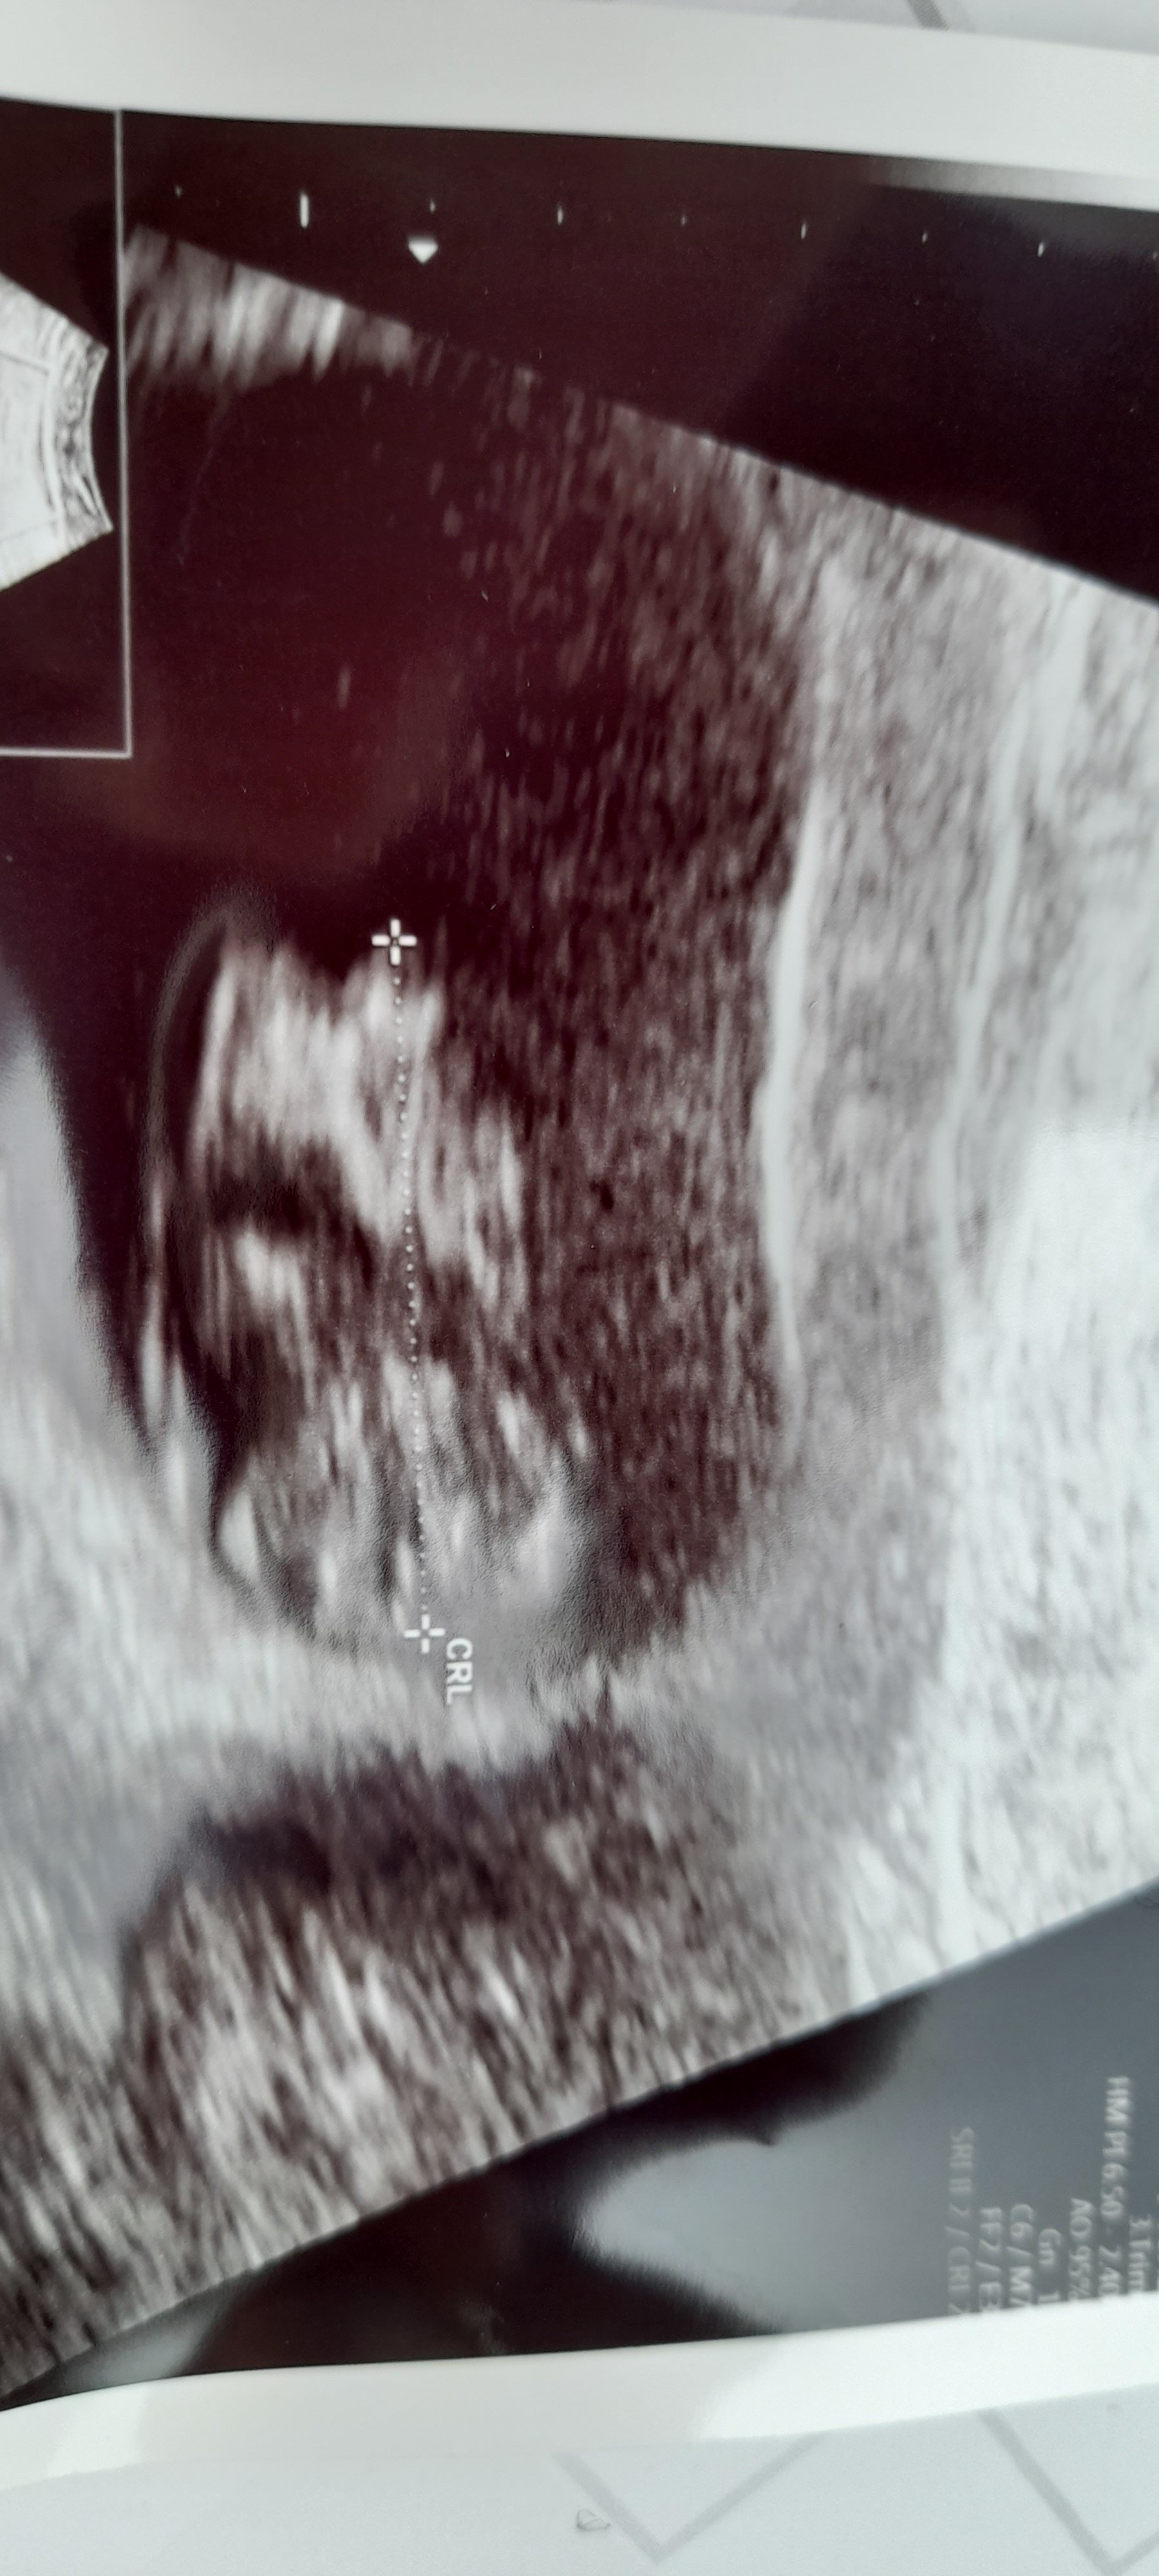

D Dilosssss Yeni Üye Üye 2 Eylül 2022 #779 Uzman SühaN' Alıntı: Merhaba , Resim yükleyebilmeniz için üye olmanız gerekiyor. Ayrıca yukarda ki görsel kadar net ise usg görüntünüz yorumlayabilirim. Genişletmek için tıkla ... Benimkinide yorumlar mısınız lütfen Ekli dosyalar IMG_20220901_164910.jpg 1,8 MB · Görüntüleme: 187

Uzman SühaN' Alıntı: Merhaba , Resim yükleyebilmeniz için üye olmanız gerekiyor. Ayrıca yukarda ki görsel kadar net ise usg görüntünüz yorumlayabilirim. Genişletmek için tıkla ... Benimkinide yorumlar mısınız lütfen